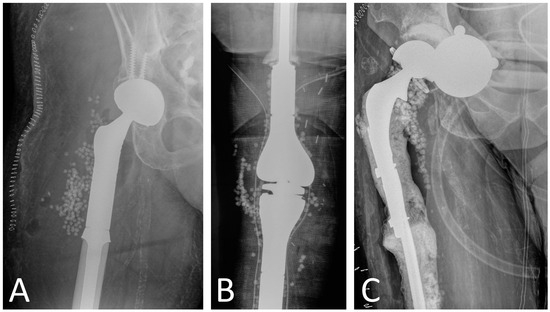

Although spacers seek to locally deliver antibiotics at high doses, studies have reported a rapid reduction to subtherapeutic levels within 24 h of implantation [80]. Absorbable calcium sulfate (CS) beads have been promoted as an alternative to traditional spacers for local antibiotic delivery. Studies have reported that CS beads provide superior elution characteristics and higher sustained antibiotic concentrations than polymethyl methacrylate (PMMA) [81,82]. Despite their superior profile in in vitro studies, clinical studies examining the use of CS beads in conventional implants for acute or acute hematogenous PJI have shown no improvement in infection eradication rates when added to DAIR procedures [83,84]. In megaprostheses PJI, there is a single study by Donati et al. in the 1990s comparing gentamicin–PMMA beads and antibiotic-impregnated cement spacers in terms of PJI treatment success [33]. This study, however, was published in the 1990s, prior to many of the surgical advances in megaprostheses and did not analyze the use of CS beads, only PMMA beads. Moreover, gentamicin–PMMA beads cannot carry other antibiotics and are, therefore, not effective against aminoglycoside-resistant bacteria. Considering the lack of studies investigating CS beads in megaprostheses (Figure 2) and the lack of information on their complication profile, we consider that their routine use is not justified.

Figure 2.

Use of calcium sulfate beads in megaprosthesis PJI as adjunct to surgical treatment in (A) proximal femur replacement, (B) distal femur replacement and proximal tibia replacement, and (C) proximal femur replacement. Patients in (A,B) underwent one-stage revision, while patient in Figure 2C had a two-stage revision.